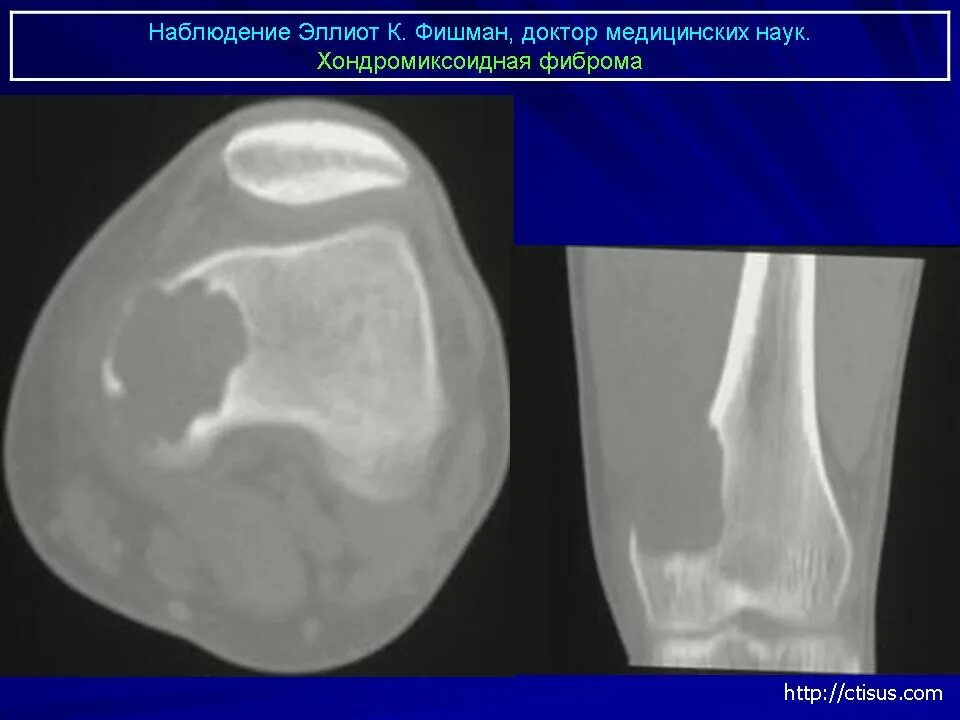

Фиброма кт